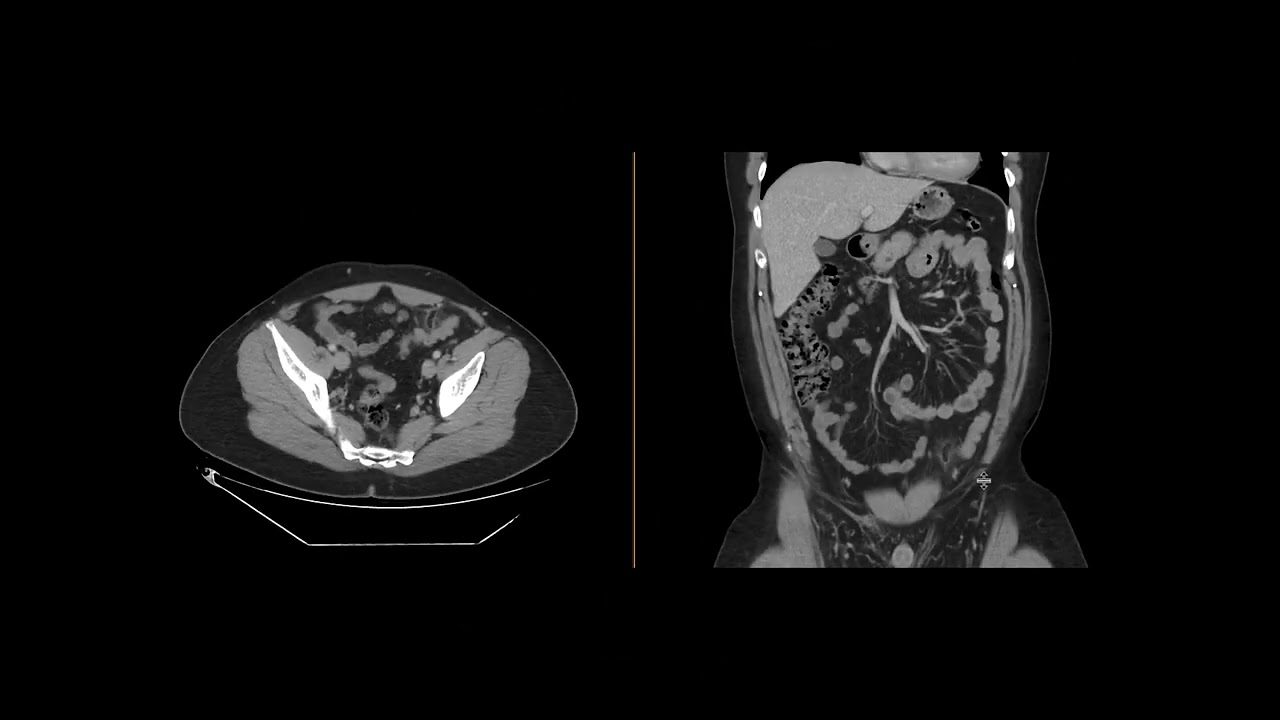

Charlotte Yoon  Presents on Epiploic Appendigitis

Chicago Telerad Extern Charlotte Yoon Presents on Epioloic Appendigits. Please join us for an exciting presentation.